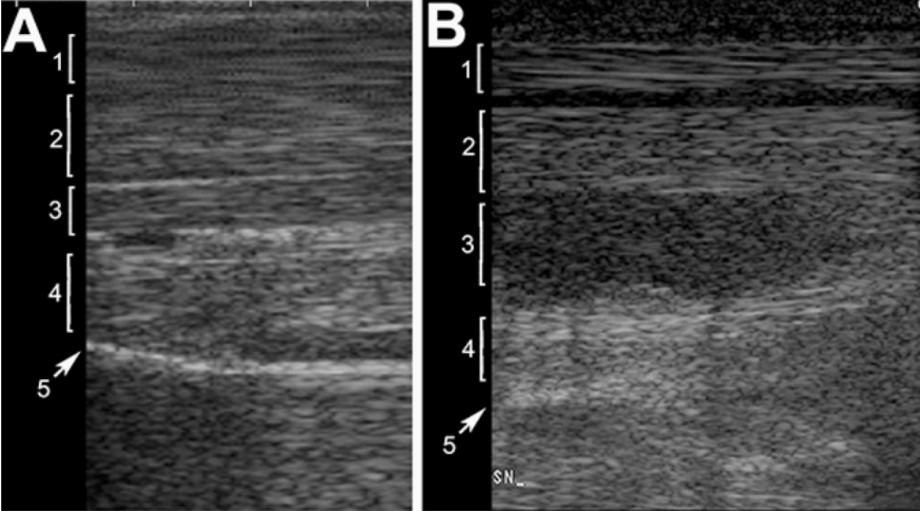

علائم اصلی اولتراسونوگرافی با خطوط A، لغزش ریه و خطوط B نشان داده می شود. خطوط A، مصنوعات(آرتیفکت) تکراری هستند که از پرتو اولتراسوند هنگام برخورد با سطح بسیار بازتابنده ناشی از محتوای فیزیولوژیکی هوای ریه سرچشمه می گیرند و در بیماران سالم مشاهده می شوند. آنها به صورت خطوط افقی، موازی و هایپراکویک ظاهر می شوند که از سطح پلورال با فواصل منظم امتداد می یابند و تمایل دارند با عمق اسکن از شدت آنها کاسته شود (طناب) لغزش ریه یک علامت سونوگرافی پویا است و از لغزش پلور احشایی بر روی پلور جداری ایجاد می شود. این حرکت نشان دهنده تماس فیزیولوژیکی دو بافت پلور است خطوط B با خطوط هایپراکوئیک که از سطح مشترک پلور شروع می شوند و عمود بر آن شروع می شوند، نشان داده می شوند که همزمان با تنفس بیمار حرکت می کنند و با همان شدت در عمق تصویر گسترش می یابند (آرتیفکت حلقه پایین). خطوط B نشان دهنده وجود سندرم ریوی آلوئولی-بینابینی است. در صورت تثبیت آلوئول، می توان برونشوگرافی هوا/مایع را مشاهده کرد. سونوگرافی قفسه سینه ابزار مهمی به ویژه در بخش مراقبت های اورژانسی است که در آن اطلاعات سریع ضروری است.

علاوه بر این، سونوگرافی قفسه سینه را می توان در معاینه ریه حیوانات بزرگ به عنوان کره اسب / اسب در نظر گرفت. هم برای حیوانات کوچک و هم بزرگ، معاینه اولتراسوند قفسه سینه در بررسی بیماری مشکوک تنفسی اندیکاسیون دارد. در حیوانات مشکوک به بیماری داخل قفسه سینه، سونوگرافی می تواند برای شناسایی پلورال افیوژن، پنوموتوراکس، بیماری پارانشیم ریوی و سایر بیماری ها استفاده شود (شکل 4).

شکل4. سونوگرافی قفسه سینه از طریق فضای بین دنده ای سمت راست در کره الاغ نر 2 ماهه ساردینیا مبتلا به پنومونی از ردوکوکوس اکوئی. رابط آکوستیک پلور یک وقفه کوتاه را نشان می دهد که ناشی از یک آبسه ریوی ساب پلورال هیپواکوی کوچک (سر پیکان خالی) است.: 1 = رابط آکوستیک پلور. 2 = A-خطوط. 3 = خطوط B.